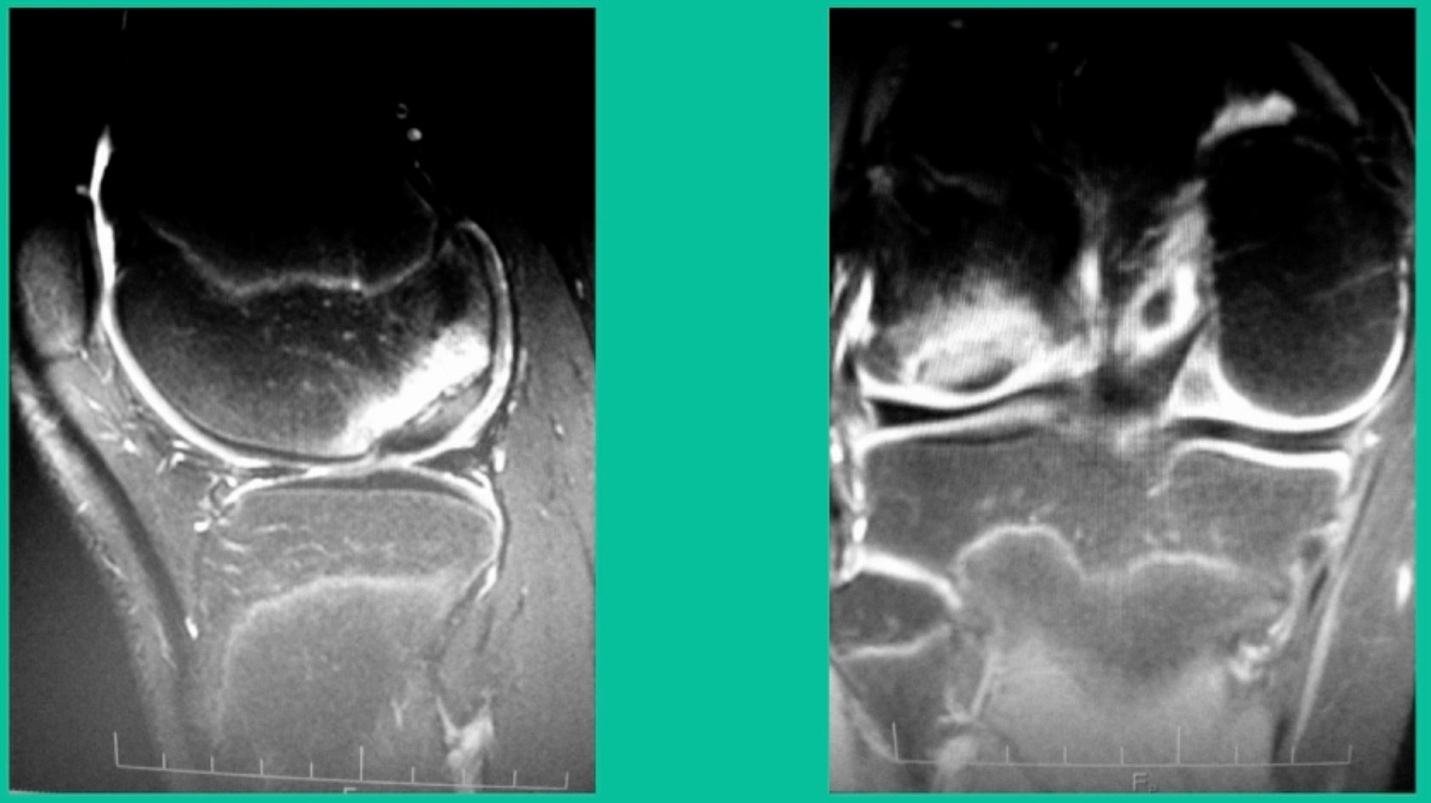

Now, we’ll shift to the adult. This is a 27-year-old. Right knee swelling, activity-related, and classic failed nonsurgical treatment on the lateral side of the knee.

This will probably be fixed. It’s a big piece and we’ll try to preserve it. The literature shows that preservation does pretty well. In this instance, there’s very little bone. It’s somewhat dystrophic, not very encouraging in my mind.

We removed it, and you say, “Well, this is terrible.” Lateral side, how is he going to do? Interestingly, the natural history does not suggest that that person will do badly. Probably the worst ones are going to be the ones who fall off to the side into the trochlea and lateral meniscus.